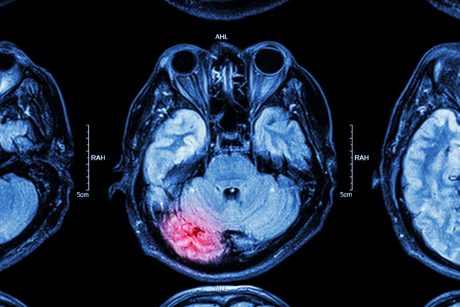

On starting treatment for his endocarditis, RS woke in hospital with a severe headache, and a scan revealed a bleed to his brain from a burst aneurysm that had developed. RS required emergency surgery to coil the aneurysm and a craniotomy to release the pressure from the swelling in his brain. Unfortunately, this resulted in permanent brain injury, cognitive impairment, dominant hand weakness and altered gait.